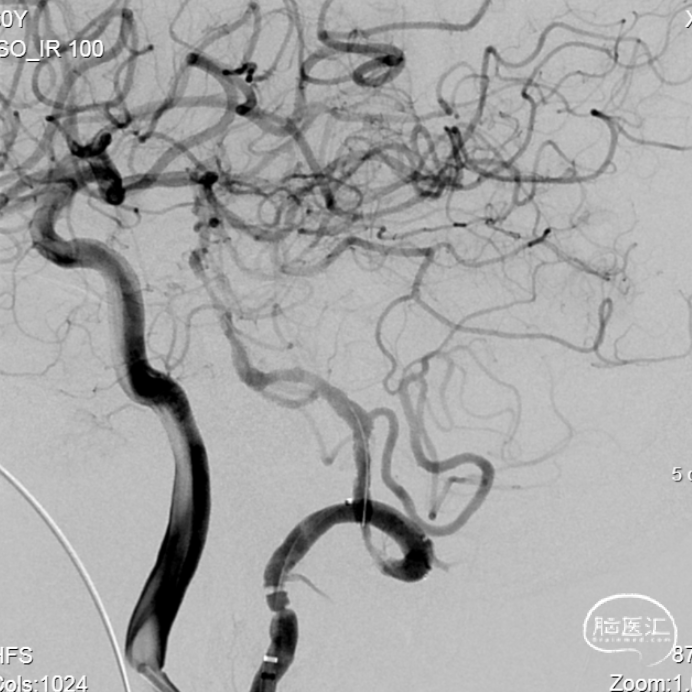

联合造影提示左侧椎基底血管再通。

观察10min后造影,支架内未见血栓,远端血流通畅,残余中度狭窄,为防止高灌注出血风险,拟二期处理。

右侧颈内动脉造影。